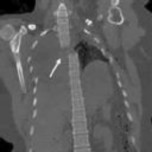

Figures 1 and 2 show a sagittal CT scan and a clinical photograph from a 16-

year-old boy who was found unresponsive after a diving accident. He had to be extricated from the bottom of a swimming pool by friends and was intubated at the scene by paramedics. In the emergency department, he was found to have weak triceps and grip strength bilaterally. Lower extremity strength was trace (grade 1 of 5). Sensation was diminished below the T2 dermatome. He had an absent bulbocavernosus reflex. Immediate open posterior reduction and stabilization were performed. Postoperative MRI revealed no iatrogenic disk herniation. Postoperative neurologic function revealed grade 4 strength in the triceps, wrist flexors, and bilateral grip. His lower extremity strength was grade 3. The sensory examination showed only slight diminution in the legs bilaterally. His bulbocavernosus reflex returned on postoperative day 2. On postoperative day 3, he required reintubation and was noted to require high positive end-expiratory pressures and a high ventilatory rate to keep him oxygenated. On postoperative day 4, his temperature was 38.7° C, blood pressure was 90/48, and pulse was 110 beats per minute. The urinary output measured 32 ml per hour. The white blood cell count was 14.8 with a left shift. A chest CT was ordered, and the results are shown in Figure 3. What best describes his condition?

4. Septic shock Discussion: D

Aspiration pneumonia developed, as seen on CT, and presumably occurred during his near drowning accident. His laboratory values and hemodynamic status are characteristic for septic shock. His original neurologic injury is an incomplete spinal cord injury, but after reduction and stabilization, he showed neurologic improvement, so this injury should not have contributed to his circulatory problems. The treatment for septic shock is broad spectrum antibiotics (species specific if the pathogen is identified) and pressors.